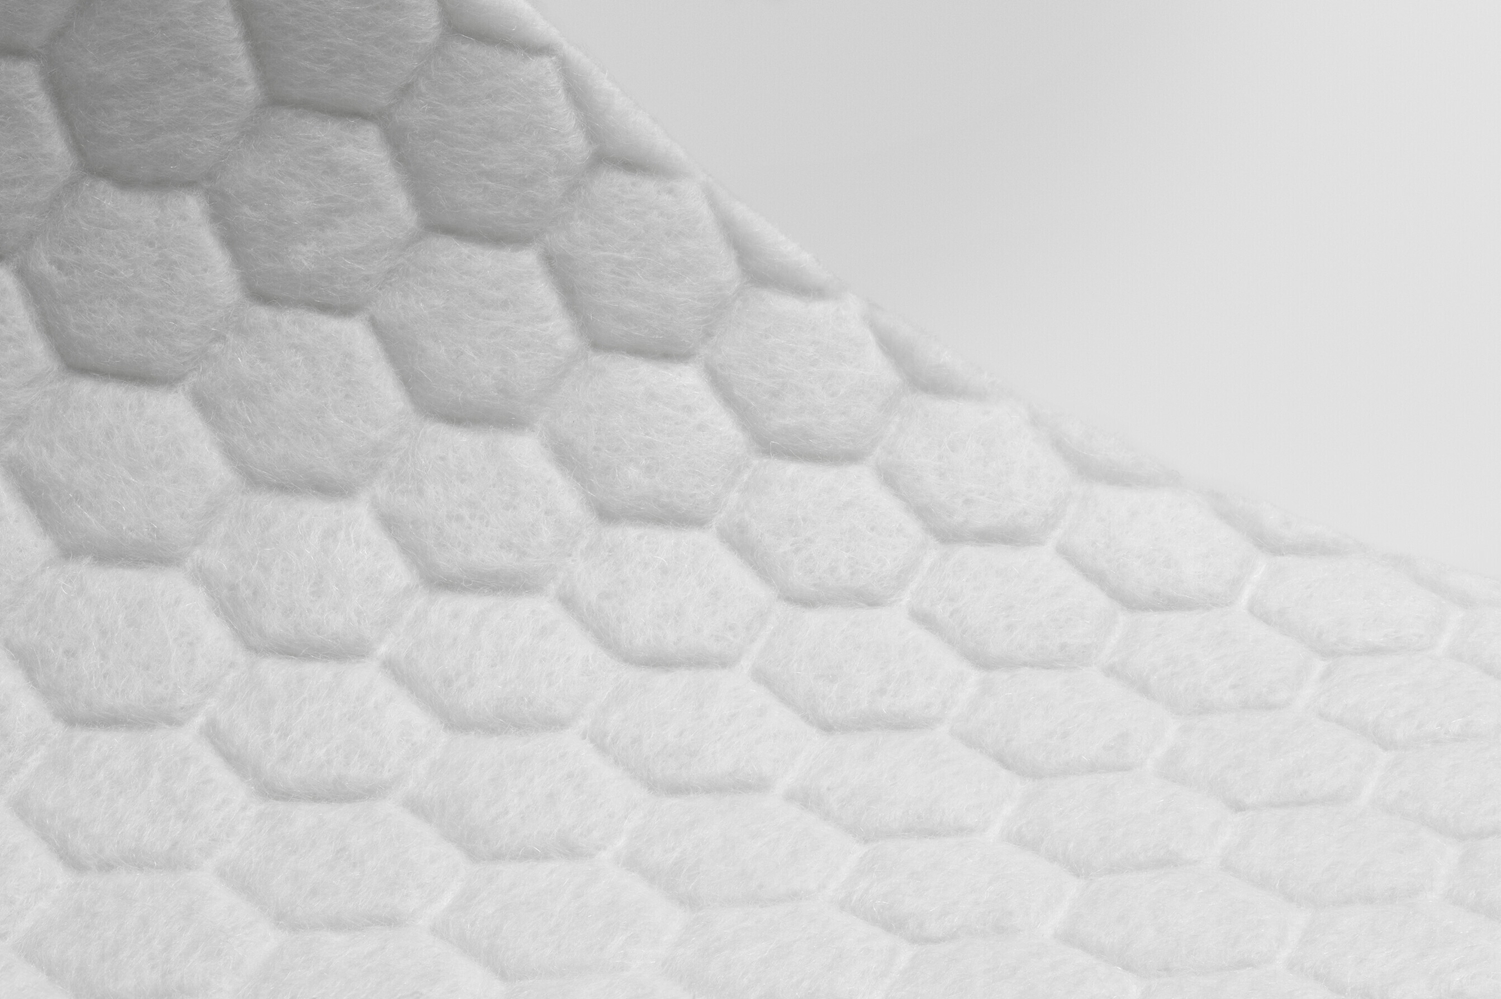

HexaLock-tekniikalla valmistettu Biatain Fiber on pehmeä, steriili ensisijainen haavasidos integroidulla vahvistuksella. Se on valmistettu ainutlaatuisesta yhdistelmästä absorboivia CMC-kuituja sekä kuituja, jotka lukitsevat eritteen ja bakteerit vahvistettuun kuusikulmaiseen verkkoon, joka vähentää eritteen jäämistä haavalle ja mahdollistaa samalla optimaalisen haavan paranemisympäristön

HexaLock-teknologia on synergia optimoidusta kuituyhdistelmästä, lämpösidonnasta ja vahvistetusta hexagon-verkosta, joka antaa Biatain Fiberille sen kyvyn tarjota optimaaliset paranemisolosuhteet haavalle.